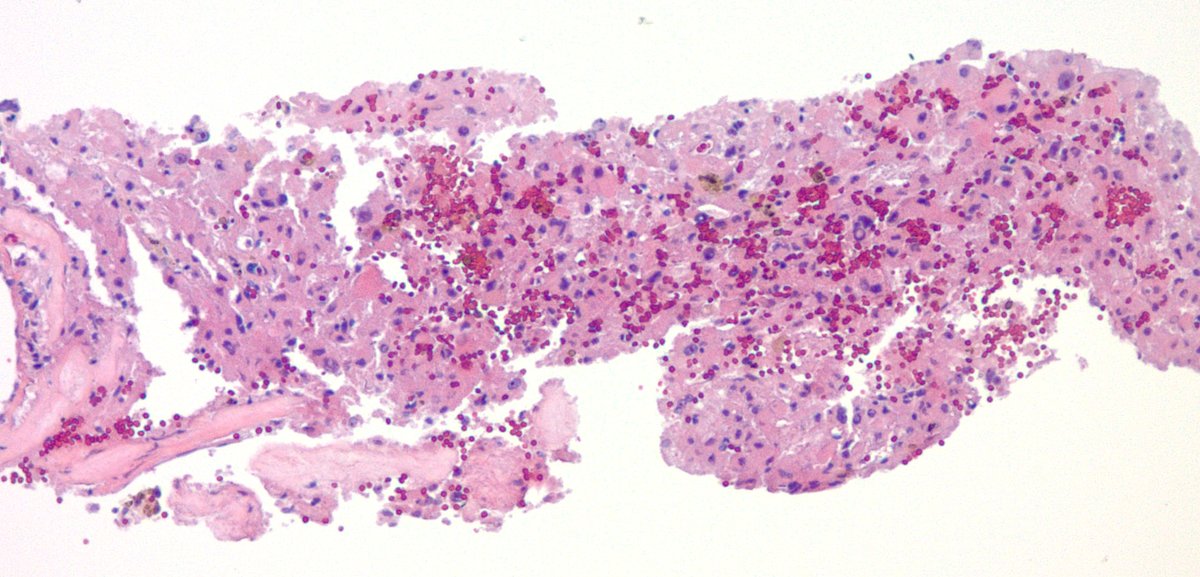

Appendix with lupus vasculitis. Appendectomy for presumed appendicitis. No acute appendicitis seen. Vessels within and outside of the appendix showed these changes with focal fibrinoid necrosis. Clinically and serologically active SLE. #GIpath #pathology

jake_bledsoe's tweet image. Appendix with lupus vasculitis. Appendectomy for presumed appendicitis. No acute appendicitis seen. Vessels within and outside of the appendix showed these changes with focal fibrinoid necrosis. Clinically and serologically active SLE. #GIpath #pathology